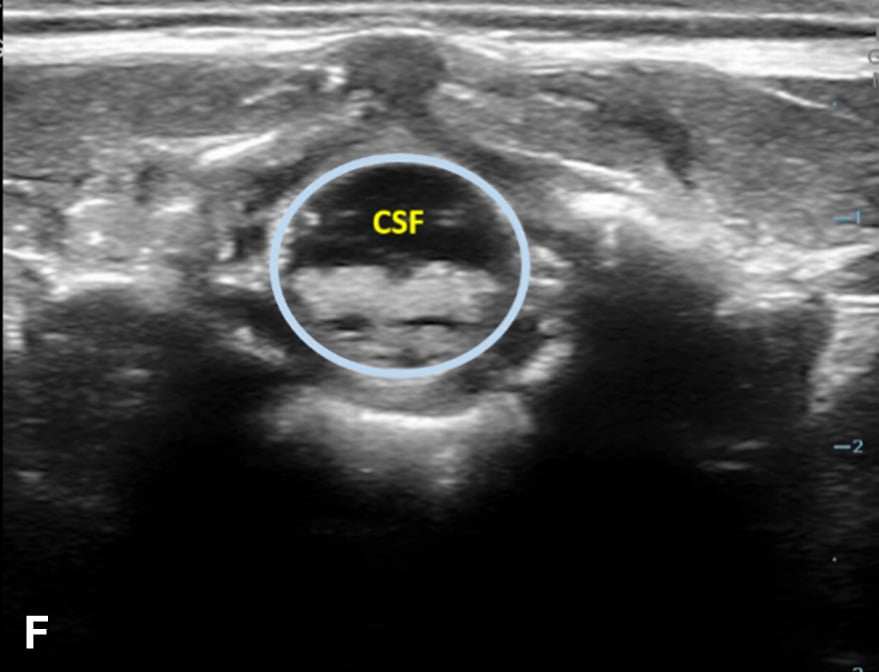

The transverse view should also be obtained to verify landmarks and identify any overlying vessels or hematomas (from prior attempts) to avoid. The transducer is rotated to the transverse position on the lower back and moved caudally over the spinous processes to locate the CM, which is a hypoechoic structure positioned in the center of the spinal canal. At higher levels of the CM, the ventral roots and dorsal roots can be identified, which are surrounded by the anechoic CSF. Next, gradually move the transducer caudally and observe the CM decreasing in size while being encircled by the hyperechoic fibers of the CE. (Figure 2) Once this sonographic landmark is identified, locate the center of the transducer and mark the corresponding area on the skin, aligning it with the center of the spinal cord. Subsequently, draw lines from both markers in both planes and utilize the point of intersection as a guide for inserting the LP needle. To enhance visualization of the spinal cord’s vascular supply, and avoid a space with any overlying vessels that may cause a traumatic tap, it is advisable to apply color Doppler in both the sagittal/longitudinal and transverse views.9 (Figure 3)

Figure 2 - Corresponding US image showing spinal canal structures in transverse view:

Figure 2 - Corresponding US image showing spinal canal structures in transverse view. 2A-B: The caudal portion of the transverse view shows DR (dorsal roots), VR (ventral roots), CSF (cerebrospinal fluid), and CM (conus medullaris). 2C-D: The probe is moved caudally demonstrating the tapered CM (orange dotted circle), CE (cauda equina, hyperechoic structure surrounding the CM) and a pocket of CSF. 2E-F: Demonstrate the disappearance of the CM, and the pocket of CSF becoming larger as the probe was moved caudally. The blue circle is the entire dural sac encircling the spinal canal.